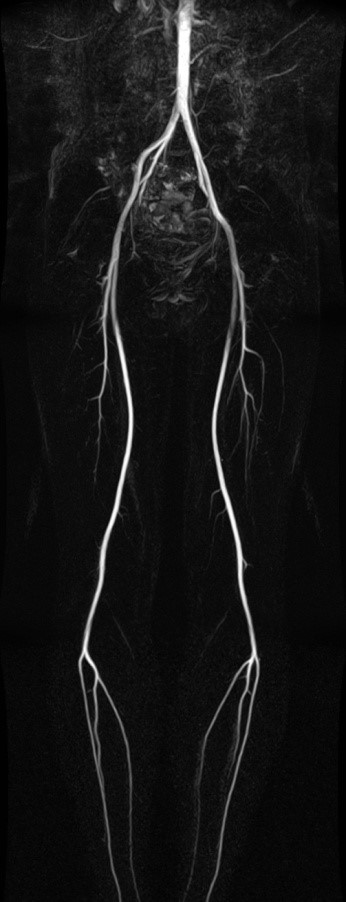

実際の画像

1.5T MRI装置(Vantage Elan)

平成27年1月新規導入。明るく開放的な空間に加え、音も静かになりストレスの少ない環境下で検査を受けていただくことができます。